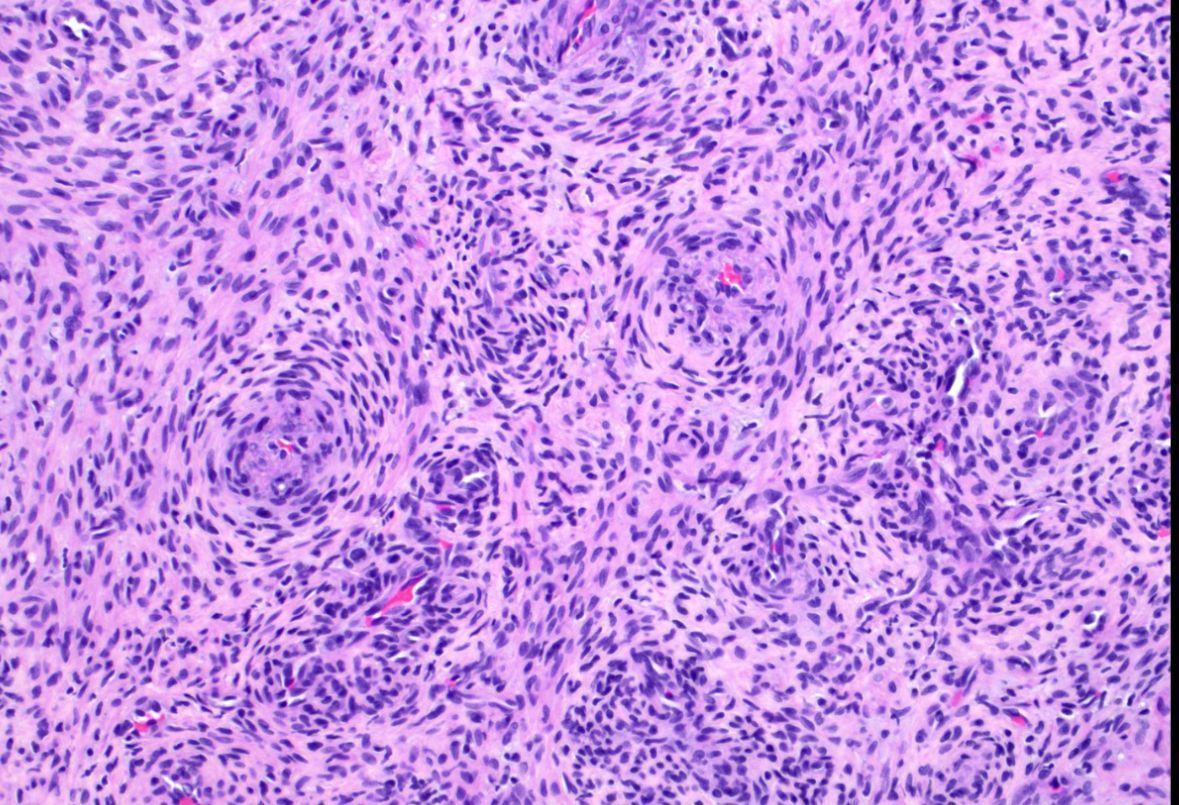

What process is happening here? How old is this patient?

Answers & pics w labels: kikoxp.com/posts/20899